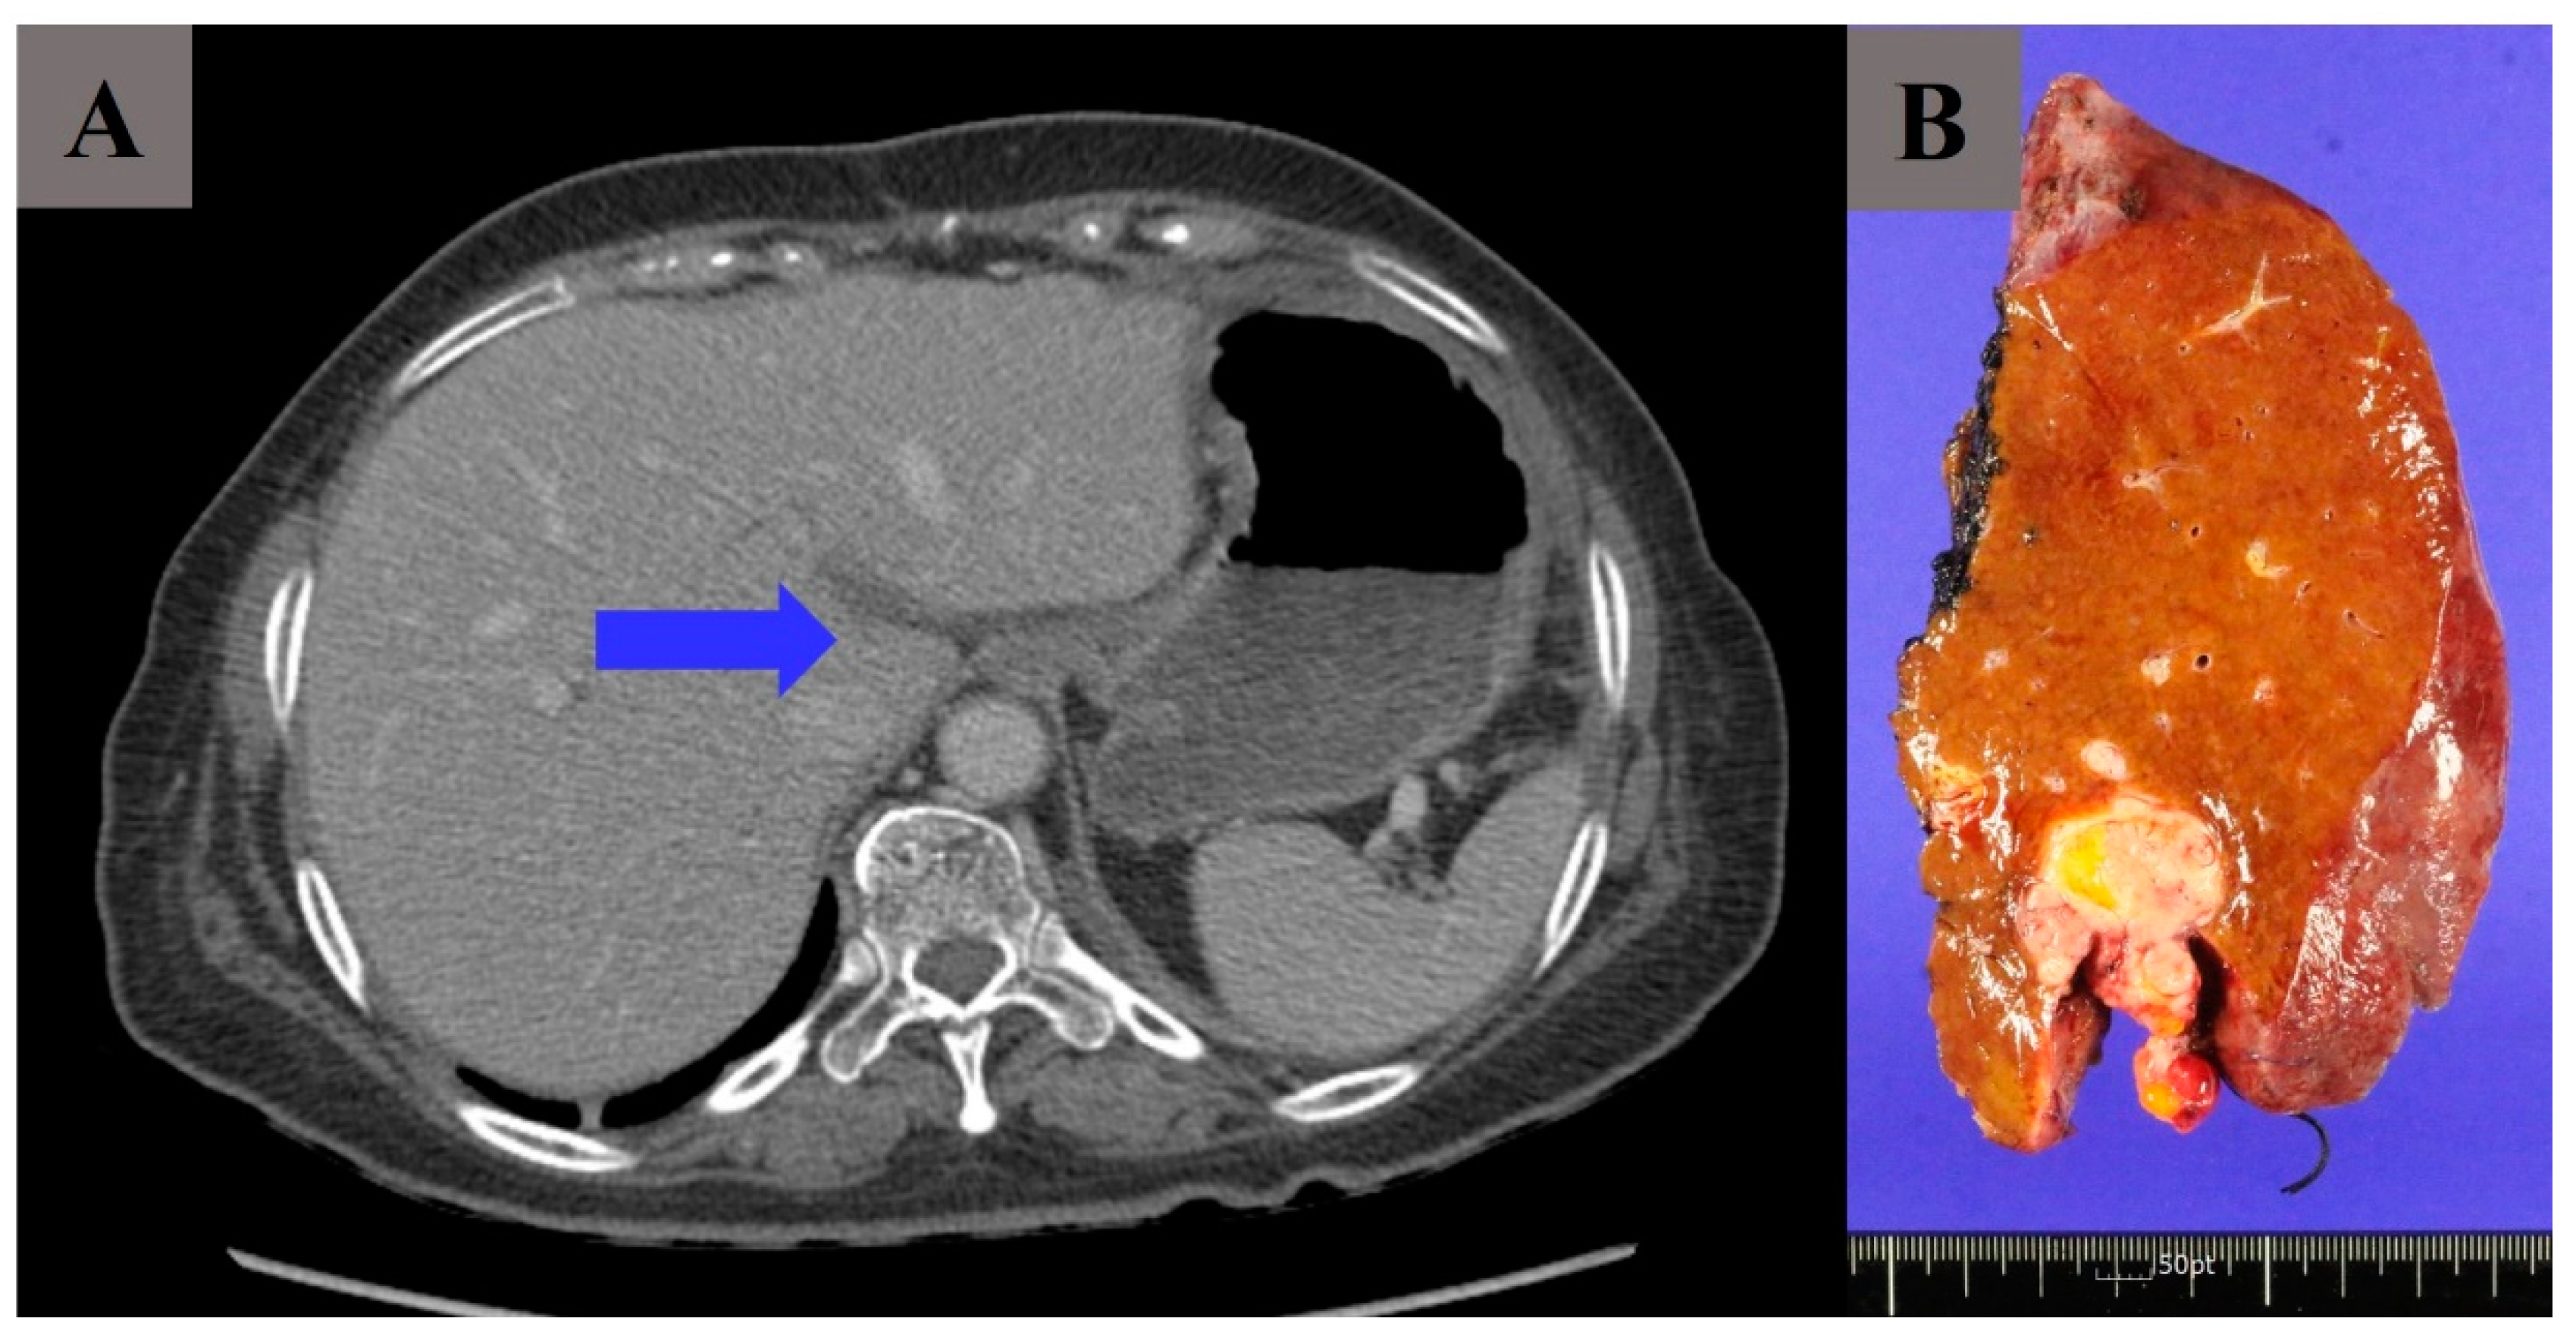

Excluding three patients (17.6%), hepatic involvement was not observed in the preoperative imaging of the remaining fourteen patients. However, tumor invasion through the round ligament of the liver was suspected intraoperatively in those patients, and left hemi-hepatectomy was performed by a hepatobiliary surgeon. It could be found in one of our cases (Figure 1). In preoperative imaging, the tumor was identified as being limited to the round ligament, not invading the hepatic parenchyma (Figure 1A). However, intraoperatively, it was identified that the tumor invasion was deeper than the preoperative image findings showed along the falciform ligament, which made left hemi-hepatectomy the inevitable choice (Figure 1B). The invasion of liver segment 4 was pathologically confirmed. Importantly, left hemi-hepatectomy is more often decided intraoperatively because deep sheet-like invasion of the tumor is found during surgery, rather than predicted preoperatively.

Figure 1.

(A) A tumor at the hepatic fissure (arrow) (round ligament of liver). (B) Surgical specimen of left hemi-hepatectomy. (A,B) are of the same patient.